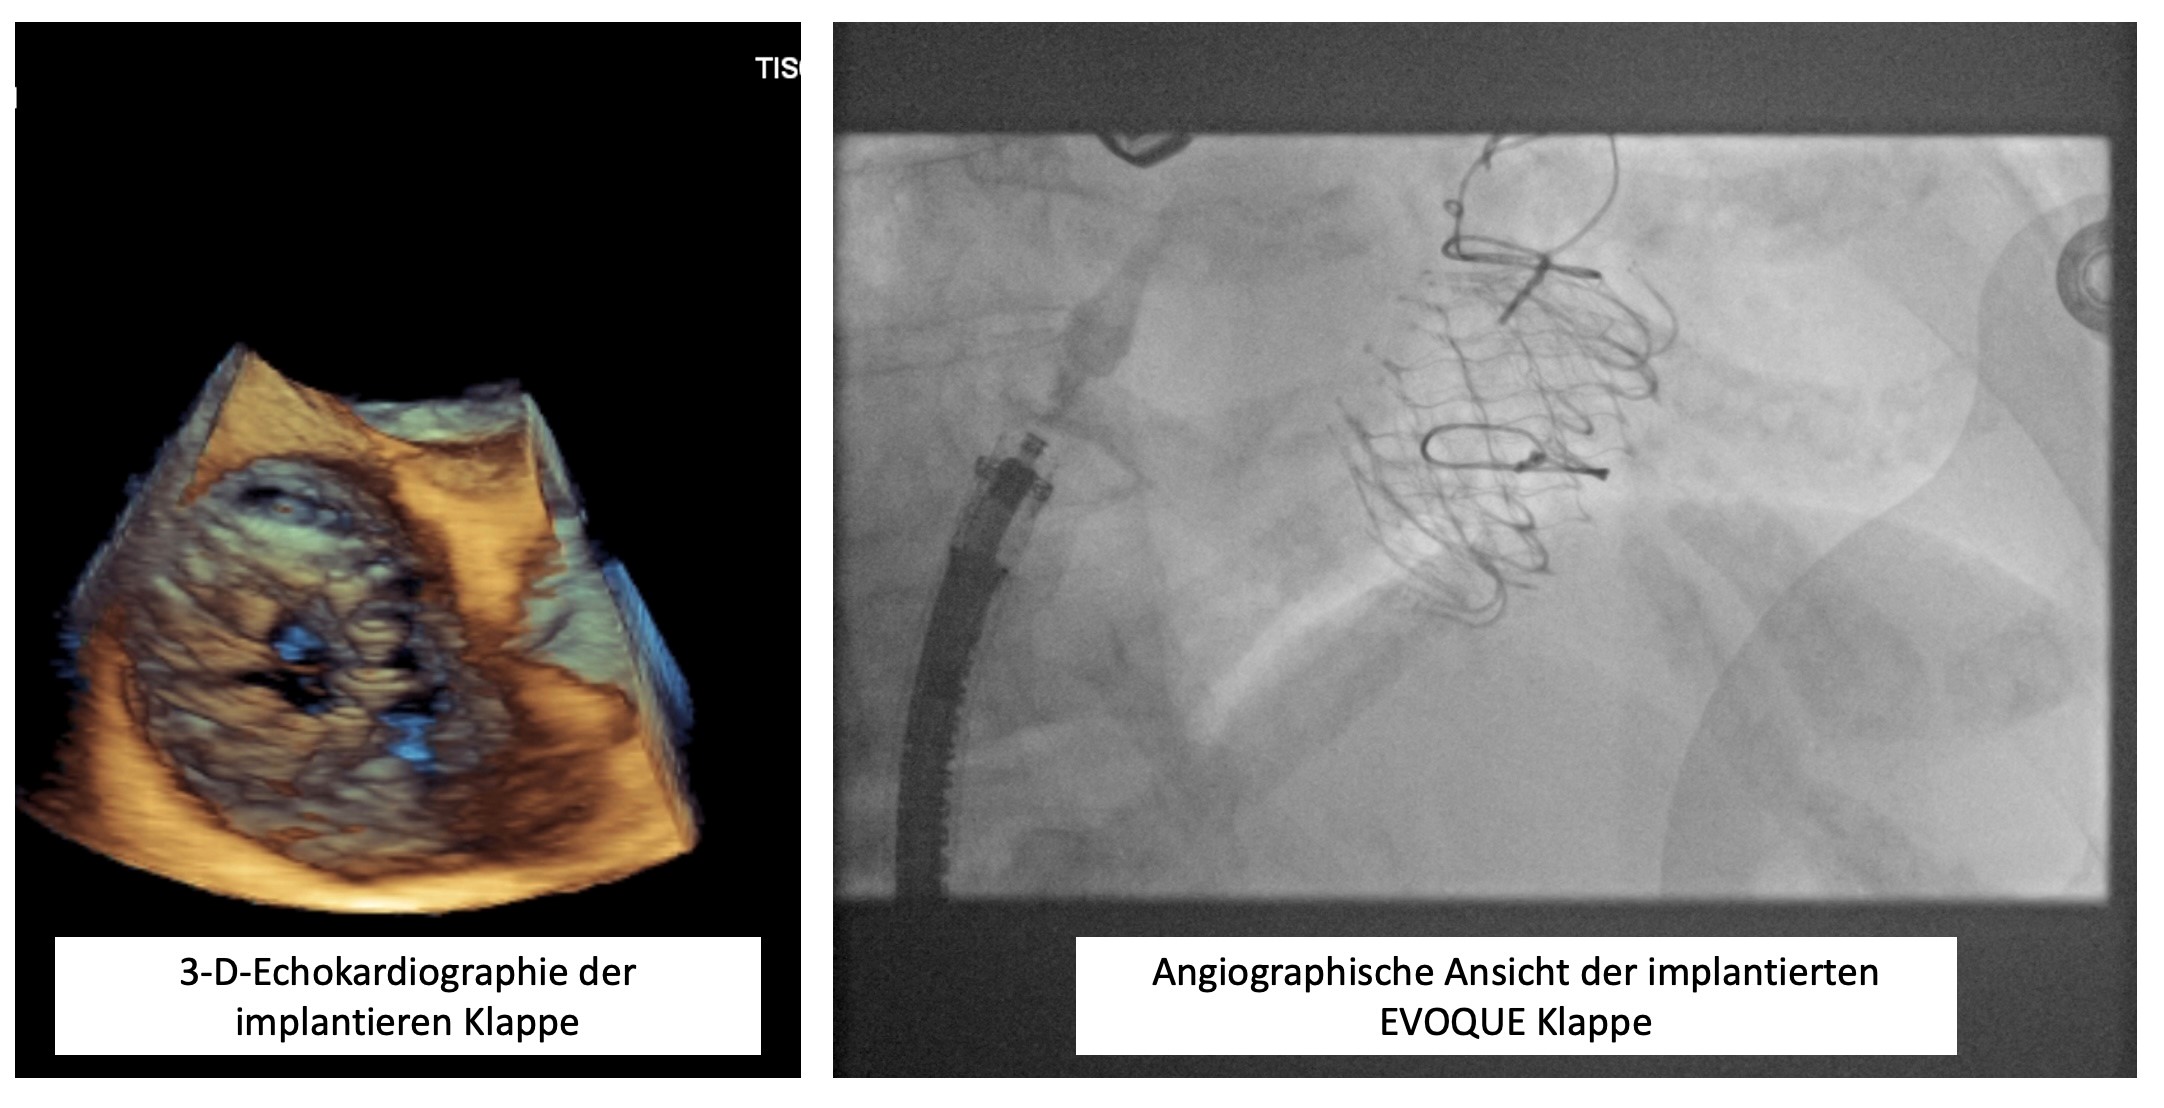

Die Trikuspidalklappeninsuffizienz (TI) ist eine häufige Klappenerkrankung, die mit einer Rückströmung von Blut aus dem rechten Ventrikel in den rechten Vorhof einhergeht. Insbesondere bei Patienten mit sekundärer TI aufgrund von Rechtsherzbelastung oder dilatativer Rechtsherzerkrankung führt dies zu belastenden Symptomen wie Rechtsherzinsuffizienz, Aszites und Ödemen. Traditionell wurde die Behandlung bei schweren Fällen chirurgisch durchgeführt, jedoch sind viele Patienten aufgrund von Komorbiditäten oder hohem Operationsrisiko für eine Operation nicht geeignet. Die interventionellen Therapieverfahren gewinnen deshalb zunehmend an Bedeutung.

Folgende interventionelle Behandlungsmöglichkeiten stehen Ihnen bei uns zur Verfügung:

- Edge-to-Edge-Repair der Trikuspidalklappe (auch T-TEER oder TricaClip genannt): Das Edge-to-Edge-Verfahren ähnelt der erfolgreichen Mitralklappen-Clip-Technik und zielt darauf ab, die Klappensegmente der Trikuspidalklappe durch eine Naht oder Clips zu verbinden, um die Klappenöffnung zu verkleinern und die Regurgitation zu reduzieren. Dabei werden die Segel mechanisch näher zusammengebracht, um den Rückfluss des Blutes zu verringern. Dieses Verfahren wird per Kathetertechnik über den Venenzugang durchgeführt und bietet eine minimal-invasive Option zur Verbesserung der Klappenfunktion bei Hochrisikopatienten.

- EVOQUE System: Das EVOQUE-System ist ein neueres, interventionelles Implantat, das direkt auf der Trikuspidalklappe fixiert wird, um eine Rekonstruktion der Klappe zu erreichen. Es zielt auf eine Wiederherstellung der Klappenschlussfähigkeit ab, ohne die Notwendigkeit einer offenen Operation. EVOQUE wird mittels transvenösem Zugang implantiert und ist speziell für Patienten mit schwerer TKI geeignet, bei denen eine Klappenreparatur durch Clips nicht ausreichend ist.

- TricValve System: Das TricValve-Konzept ist eine interventionelle Therapie, die sich bei schweren Fällen von Trikuspidalklappeninsuffizienz mit nicht reparabler Klappenstruktur auf die Implantation von bioprothetischen Klappen im Venensystem (Vena cava superior und inferior) konzentriert. Ziel ist es, den Rückfluss von Blut in die systemische Venenzirkulation zu verhindern und so die Symptome der Rechtsherzinsuffizienz zu lindern. Dieses Verfahren ist eine palliative Maßnahme, die insbesondere bei Patienten mit hohem Operationsrisiko eingesetzt wird.

Die interventionelle Therapie der Trikuspidalklappeninsuffizienz erweitert das Behandlungsspektrum erheblich und bietet Patienten mit bisher limitierten Optionen neue Hoffnung auf Symptomlinderung und Lebensqualitätsverbesserung. Die Wahl des geeigneten Verfahrens richtet sich nach dem individuellen Krankheitsbild, der Anatomie der Klappe und dem klinischen Zustand des Patienten.